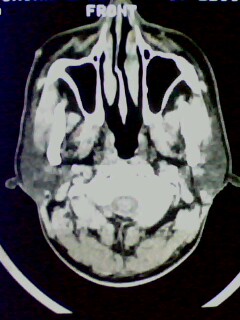

以下是引用随光逐影在2009-5-20 19:22:00的发言:[br]1)考虑左上颌骨近中线区含牙囊肿。2)鼻中隔右突偏曲。3)双侧下鼻甲肥大。